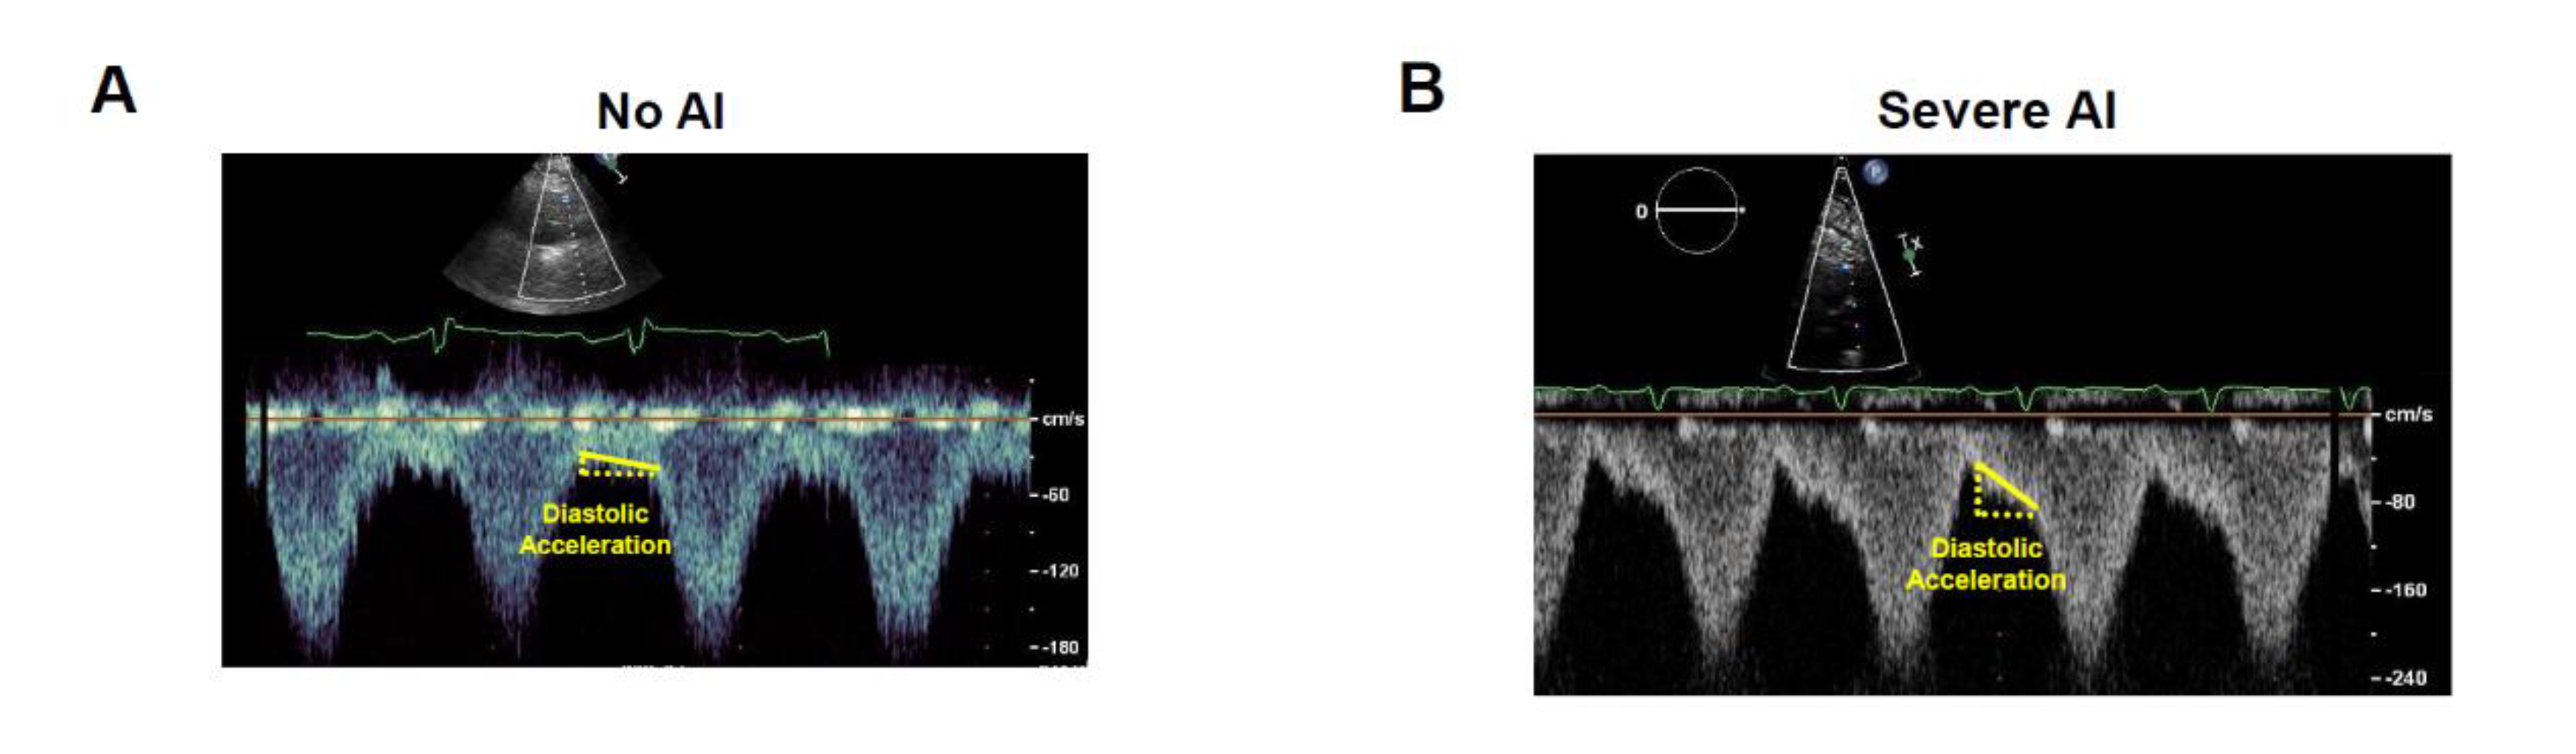

- Grinstein, J.; Kruse, E.; Sayer, G.; Fedson, S.; Kim, G.H.; Jorde, U.P.; Juricek, C.; Ota, T.; Jeevanandam, V.; Lang, R.M.; et al. Accurate quantification methods for aortic insufficiency severity in patients with LVAD: Role of diastolic flow acceleration and systolic-to-diastolic peak velocity ratio of outflow cannula. JACC Cardiovasc. Imaging 2016, 9, 641–651. [Google Scholar] [CrossRef] [PubMed]